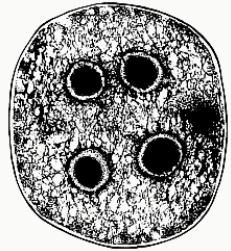

Entamoeba coli (cyst)

Entamoeba coli (cyst)